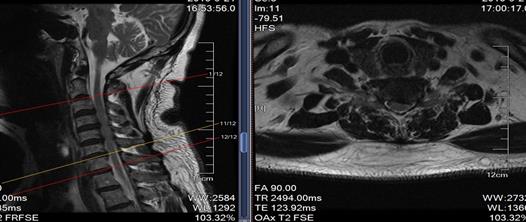

从术前的腰椎磁共振我们可以看到腰椎向下脱垂游离的巨大间盘突出,压迫右侧神经根,我们给她做了后路脊柱内镜下腰椎间盘摘除术。

术后第二天复查腰椎磁共振我们可以看到脱垂的间盘组织被完整的摘除,术后当即患者的症状就消失了,可谓立竿见影。

这是一例胸7-8间盘突出的患者,患者下肢无力越来越重,已经到了不能走路的地步,必须手术才能解决,可是胸椎手术风险比腰椎大的多,是真有可能瘫痪的,我们顶住压力,为了患者的健康着想,为他做了脊柱内镜下胸椎间盘摘除术。